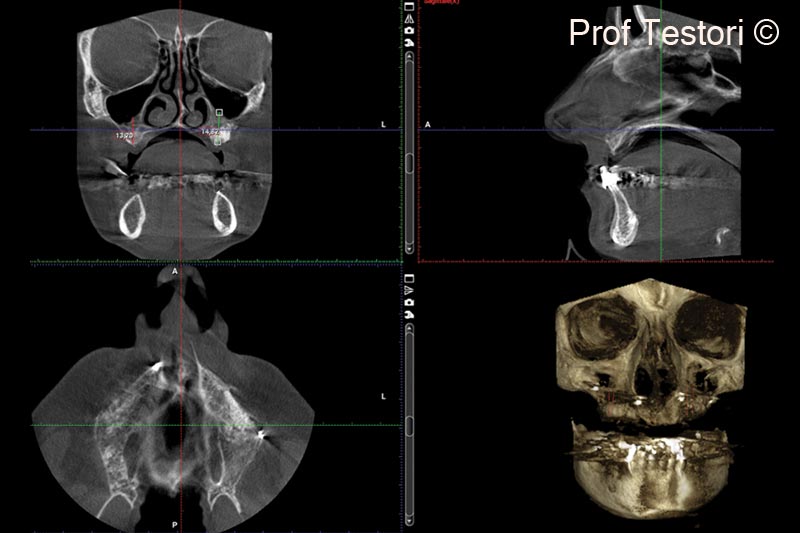

13. 6-months follow-up CBCT performed before implant placement